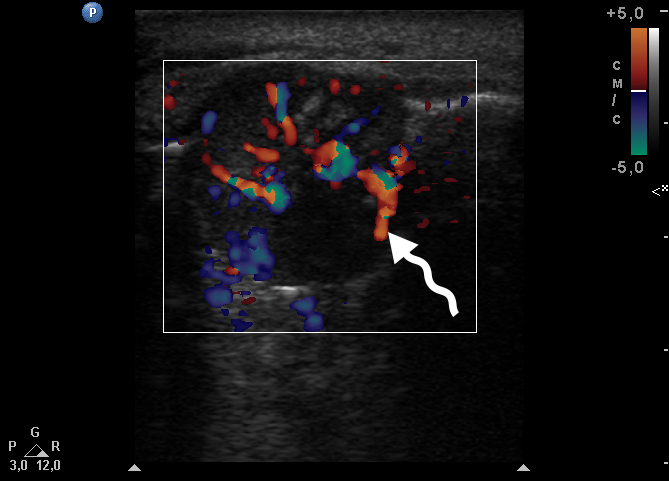

Color Doppler USG (Fig 5) showed prominent intralesional vascularity. Figure 6 demonstrates gray-scale USG of the lesion from two different angles, which allows for better visualization of echogenic areas (i.e., areas of ossification) within the lesion. It was not possible to adequately determine the area of the “stem” of the lesion.

During the complete surgical excision of the lesion (V.H.D.) followed by a peripheral osteotomy, profuse bleeding was noted both from the soft tissues and from the bone tissue of the alveolar ridge. This significant bleeding is confirmation of the color Doppler data on the presence of increased vascularization within the lesion.

In our case, we applied transfacial USG (i.e., indirect USG) (Gad et al., 2018) for examination of the lesion and surrounding tissues [28]. The case we presented confirms the data that an advanced vascularization is frequently seen in PGCG upon Doppler examination [11].

Thus, our case allows to add two important ultrasound differential features for PGCG located in the anterior edentulous mandible compared to other reactive alveolar ridge pathology. Namely, areas of bone formation and prominent intralesional vascularity.